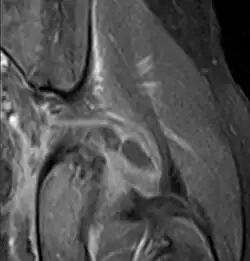

| Transverse T2 magnetic resonance imaging section through the hip region showing abscess collection in a patient with pyomyositis. | |

Axial T1 weighted fat suppressed post IV gadolinium contrast enhanced MRI image showing a mutliloculated bacterial abscess in the left gluteal muscle which grew Staphylococcus aureus (methicillin sensitive) thought to be due to tropical pyomyositis.

Coronal fat suppressed post contrast image showing a multiloculated bacterial abscess in the left gluteus minimus muscle due to tropical pyomyositis.

Coronal T2 weighted fat suppressed image showing a multiloculated fluid collection in the left gluteal musculature due to tropical pyomositis in a 12-year-old boy.